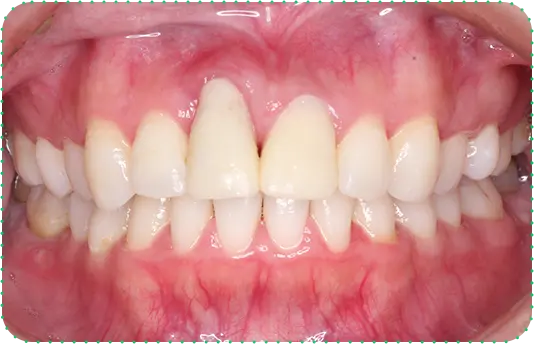

Before

After

主訴

前歯をインプラントにしてほしい

治療期間

8か月

治療費

約150万円

治療内容

右上1番と左上1番をインプラント、右上2番をラミネートべニア、左上2番をセラミッククラウンにて修復

治療のリスク

治療後に口腔内管理が不適切な場合、埋入したインプラントが感染・炎症を起こす可能性があります。

しみたり、違和感が生じることがあります。咬み合わせによっては、セラミックが欠ける可能性があります。